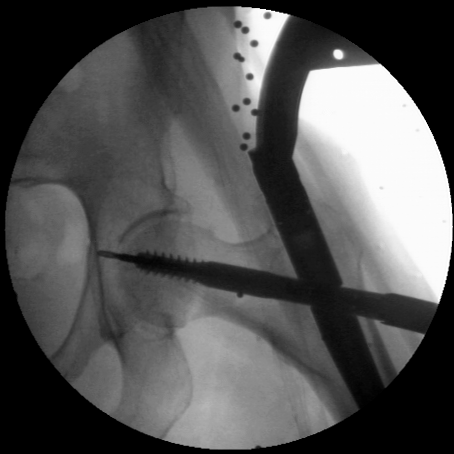

To evaluate the performance of our proposed method we choose a challenging segmentation task: the contour of the femur in fluoroscopic (low-dose) X-ray images. The quality of this image modality is low and thus the performance of the standard ASM algorithm suffers. Our database contains 350 gray-scale images that have been acquired during surgeries treating hip fractures in an approximate anterior-posterior orientation. These images show the upper part of the femur and part of the hip. They belong to different surgical interventions and C-arm devices. The image sizes range between 450x450 to 510x510 pixels. We have a ground truth consisting of a manually segmented femur contour and landmarks for every image. We show one of these images in Fig.ย 1. As these images come from surgeries treating hip fractures, they contain an intermedullary nail and a screw, which further complicate the segmentation task with occlusions.

Refer to caption15811202426323540landmarks of the PDMscrewnail

Fig.ย 1: Landmarks of a PDM (1 to 40) of the femur in a fluroscopic X-ray image in anterior-posterior orientation.